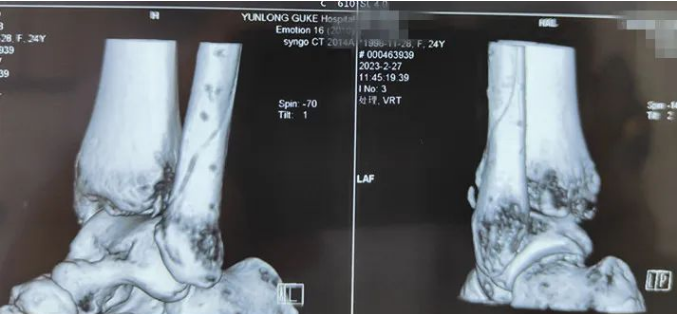

患者柯某某,女,58 岁,因外伤致右踝关节损伤,入院诊断为右内外踝骨折伴踝关节脱位,受伤后踝关节肿胀明显,给予系统性治疗,6天后消肿,手术前手足显微外科室多次讨论、综合评估、完善术前准备,制定了详细手术方案。由于担心自己年龄较大,患者不想二次进行手术取出金属内固定,选择可吸收钉板进行手术。在麻醉科的配合下用时近2小时左右顺利完成手术,术后拍片显示骨折及关节达到临床复位。

右内外踝骨折伴踝关节脱位术前